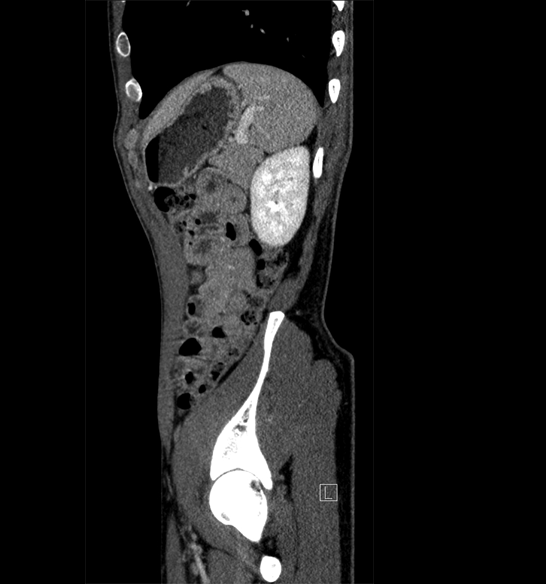

Body

Covers abdominal CT anatomy.